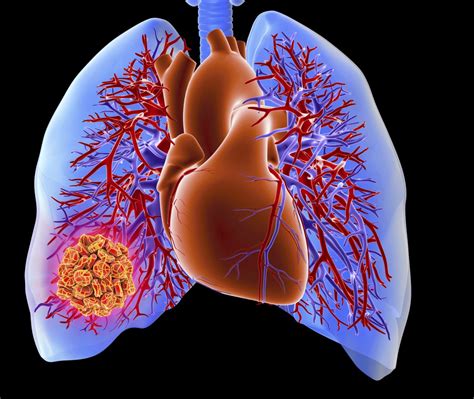

Understanding the Signs Of A PE (Pulmonary Embolism) is crucial for timely intervention and effective treatment. A PE occurs when a blood clot, typically from the legs, travels to the lungs and blocks an artery. This condition can be life-threatening if not addressed promptly. Recognizing the early Signs Of A PE can save lives, making it essential for both healthcare professionals and the general public to be aware of the symptoms and risk factors.

A Pulmonary Embolism (PE) is a blockage in one of the pulmonary arteries in the lungs. This blockage is usually caused by a blood clot that travels from another part of the body, most commonly from the deep veins in the legs, a condition known as deep vein thrombosis (DVT). When a clot breaks loose and moves to the lungs, it can obstruct blood flow, leading to serious complications.